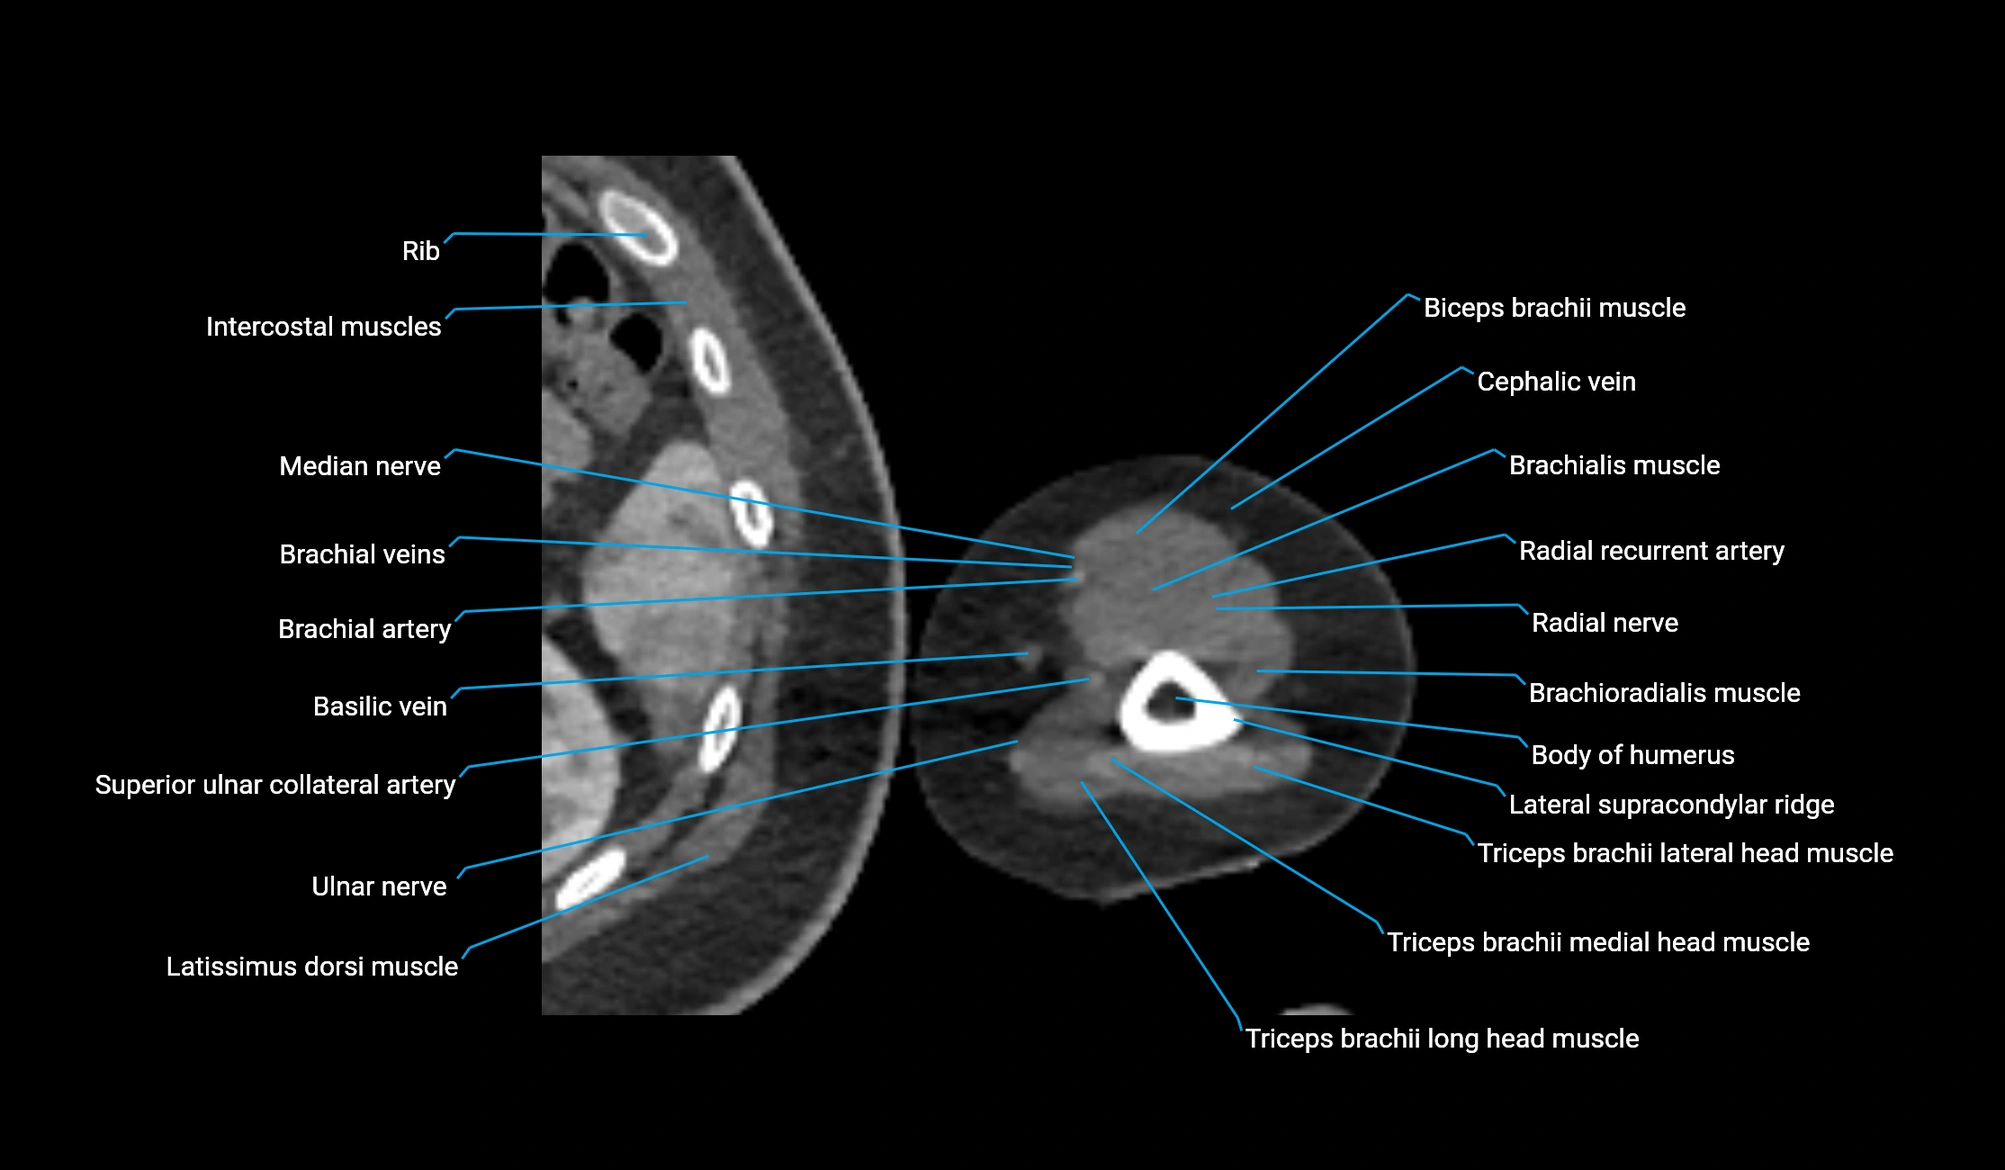

CT image